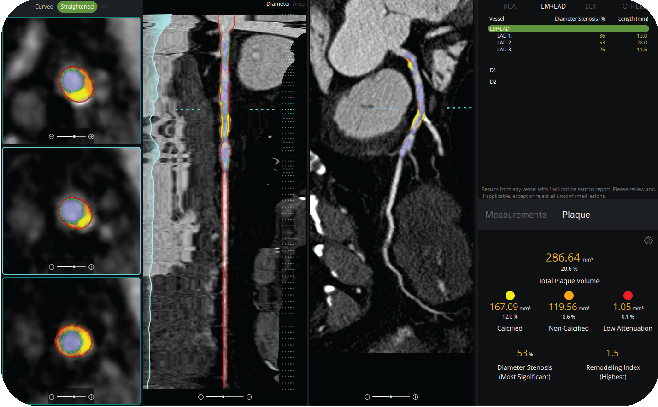

The semi-automated coronary lumen segmentation and plaque quantification

tools provide detailed per-vessel and global measurements, including:

• Calcified plaque volume and burden

• Non-calcified plaque volume

• Low-attenuation, or vulnerable, plaque assessment

All measurements remain editable and user adjustable. Clinicians maintain full oversight of the final report while benefiting from AI-supported software. The result is a reproducible approach that improves consistency between studies and clinicians, while also strengthening longitudinal tracking of disease progression.